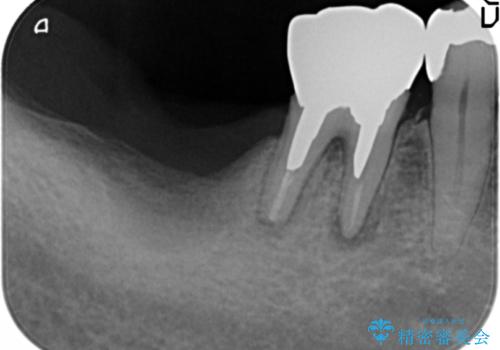

骨が少なく下顎神経に近いことから、他院でインプラントできないと言われたとのことでした。

骨増生(GBR)を行い骨を増やすことでインプラント治療を可能にしました。

インプラントの種類:スプライン ツイスト (HAコーティング)

固定様式:セメント固定